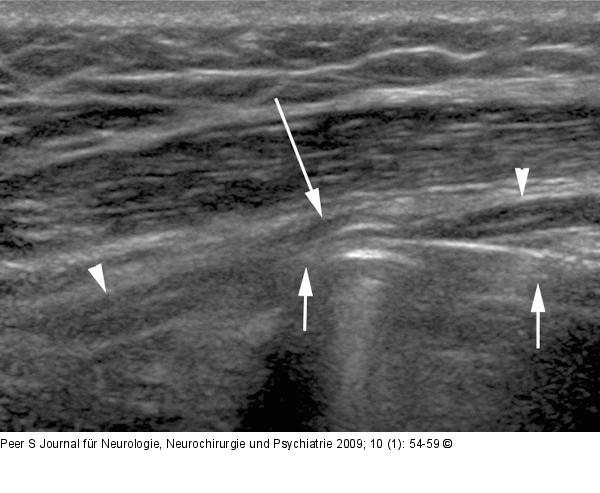

Abbildung 7: Nervus radialis Sonographischer Längsschnitt durch den Nervus radialis (Pfeilspitzen) bei einem Patienten mit Radialisparese nach operativer Versorgung einer Humerusschaftfraktur. Der Nerv wird durch die vom Knochen etwas abstehende Platte (kurze Pfeile) abgedrängt und komprimiert (langer Pfeil). |

Sonographischer Längsschnitt durch den Nervus radialis (Pfeilspitzen) bei einem Patienten mit Radialisparese nach operativer Versorgung einer Humerusschaftfraktur. Der Nerv wird durch die vom Knochen etwas abstehende Platte (kurze Pfeile) abgedrängt und komprimiert (langer Pfeil). |